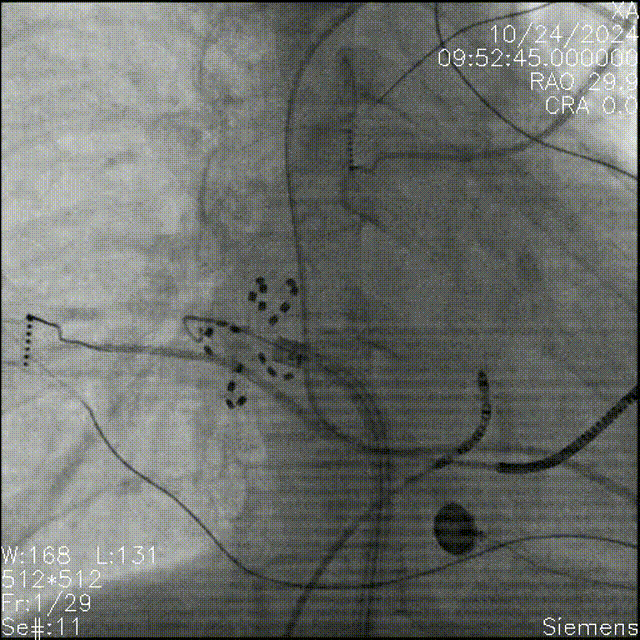

FARAPULSE导管花瓣消融

左心耳封堵器完美封堵